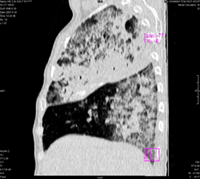

女67岁,咳嗽咯白痰伴纳差一月。右肺呼吸音低可闻及湿罗音。白细胞及淋巴细胞不高,无发烧

1、右上胸廓塌陷,纵隔气管右移

2、病灶靠后方,一般结核多见一点

3、病灶内,纵隔内有少许钙化灶

3楼的肺细支气管肺泡癌也不能完全排除,毕竟患者年纪大,病史短,临床上感染症状不明显,建议短期内复查吧